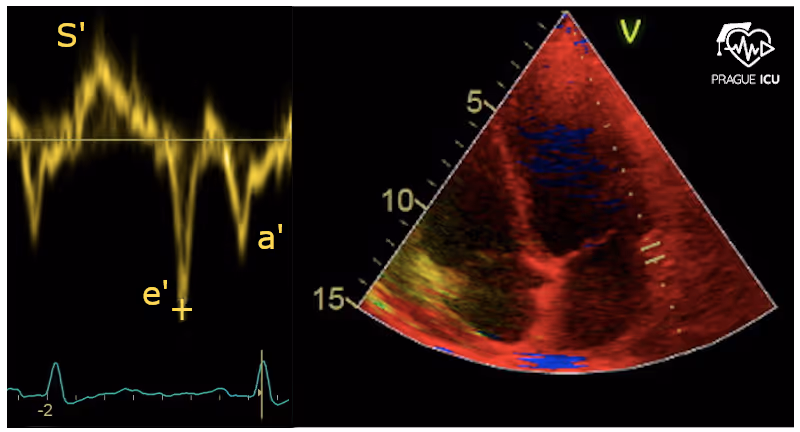

3.2.2 Tkáňový doppler pro hodnocení diastolické dysfunkce

Pohyb prstence mitrální chlopně odráží systolické a také diastolické děje.

Ve 4dutinové projekci lze pohyb anulu zobrazit pomocí PW tkáňového dopplera (TDI) na mediálním (septálním) i laterálním prstenci.

Co můžete změřit pomocí rychlosti pohybu mitrálního prstence v zobrazení tkáňového dopplera (TDI)?

Na dopplerovském zobrazení představuje diastolický signál negativní výchylku.

Stejně jako při běžném pulzním dopplerovském zobrazení je přítomna vlna E a vlna A.

Při tkáňovém dopplerovském zobrazování se nazývají e´ (e prime) a a´ (a prime).

Septální a laterální vrcholová časná diastolická rychlost mitrálního prstence (e´)

Hlavním určujícím faktorem e′, časné diastolické rychlosti pohybu mitrálního prstence, je relaxace LK.

Odráží prodloužení LK a je ovlivněna preloadem.

Podélná rychlost e′ levé komory s věkem klesá.

Normální rychlost e' ≥ 7 cm/s (med) a 10 cm/s (lat).

Obrázek č. 18 Pohyb septálního mitrálního prstence pomocí tkáňového dopplera (TDI), S′ = systolický pohyb, e´ a a´ = diastolický pohyb.